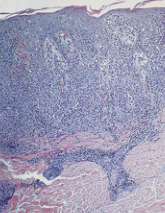

In the radial growth phase, cells grow in all directions. In the vertical growth phase, the dominant direction of tumor growth shifts to the dermis.

The most important prognostic factor is the depth of invasion.

BRAF V-600E mutations are common.

(image displays radial growth phase)

A

Malignant Melanoma

(image displays vertical growth phase)